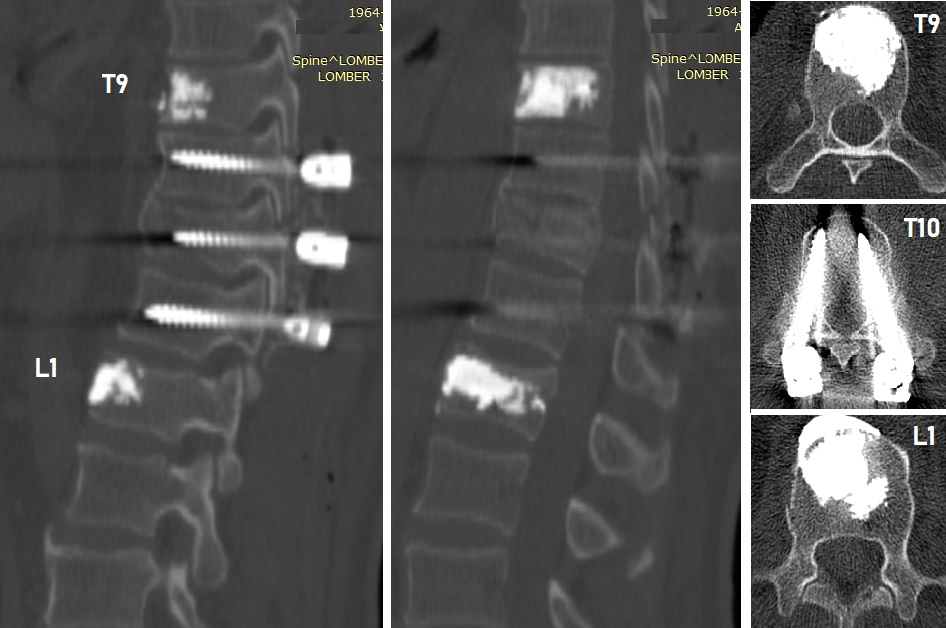

Postoperatif Direkt Grafi - Kifoplasti ve Stabilizasyon

Resim 4: Ameliyat sonrası (postop) direkt grafilerde T9 ve L1 kifoplasti, T10-11-12 transpediküler stabilizasyon görülmektedir.

Hastaya T9 ve L1 vertebralarına kifoplasti (6'şar ml metilmetakrilat) ve T10-11-12 vertebralarına transpediküler stabilizasyon uygulandı. Laminalar ve fasetler üzeri kısmi dekortike edilerek füzyon artırıcı (Ca-fosfat granül) materyal ve alandan alınan otojen kemikler serildi. T11 laminası ve faset ekleminin iki yanlı kırık olduğu görüldü. Laminektomi yapılmadı.